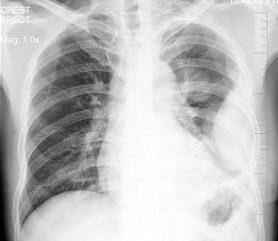

16、问答题 肺不张的X线表现有哪些?

87、单项选择题

男,12岁,平时无明显不适,结合图像,最可能的诊断是()

A.正常胸片

B.左旋心

C.右旋心

D.镜面右位心

E.以上都不是